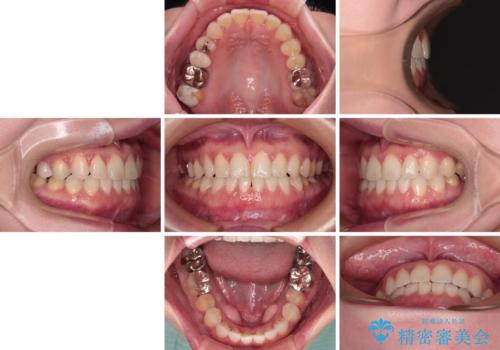

前歯のデコボコをすっきりと インビザライン矯正

- 前歯のデコボコを治したいとのことで来院された患者様です。

下顎が前方位にある方であったため、下顎の歯列全体の後方移動とIPR(歯と歯の間を削る)によってデコボコが解消するように設計し、インビザラインにより治療を行うこととしました。

装着時間が守れず、当初の予定よりも長期間必要となりました。